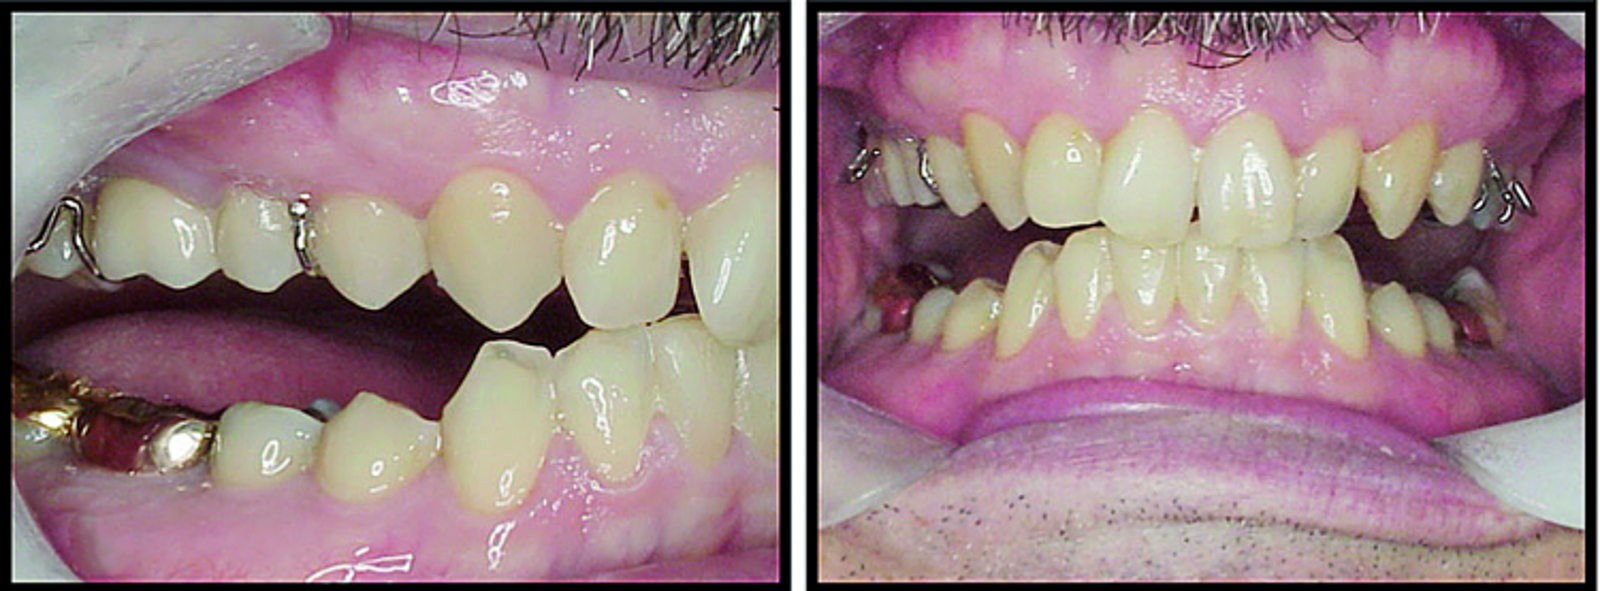

BiTurbo2 system for rapid deep overbite correction